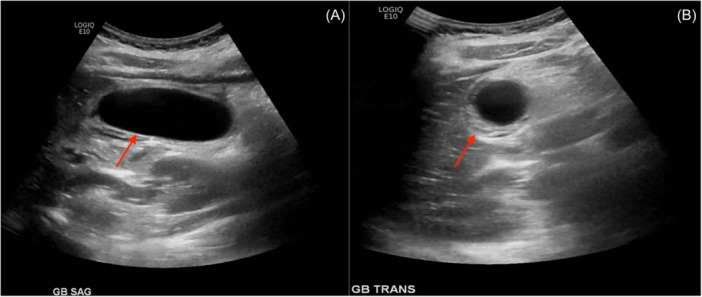

Gallbladder volvulus (GV) involves the rotation of the gallbladder along its axis, resulting in torsion. This pathology is rare, more commonly found in elderly females, but can occasionally occur in pediatric patients. Diagnosis is challenging due to often atypical symptoms, with imaging and laboratory findings typically nonspecific. Prompt surgical intervention is necessary when GV is suspected to prevent significant systemic illness. Laparoscopic cholecystectomy has proven to be safe and effective in pediatric cases. In this report, we present a pediatric case of GV, initially misdiagnosed as viral-induced acalculous cholecystitis, which was effectively managed using laparoscopic cholecystectomy.